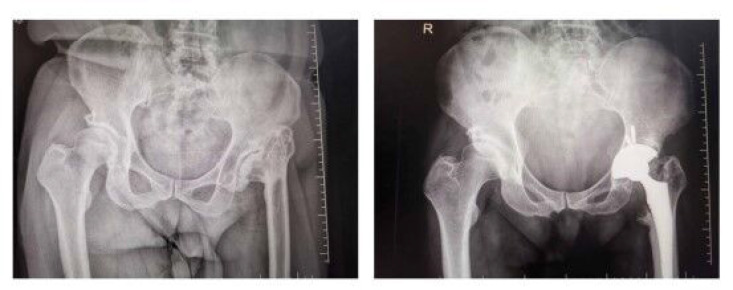

Objectives: Total hip arthroplasty (THA) is a highly successful and effective surgery for improving hip functions and relieving pain. However, the lower extremities are prone to deep vein thrombosis (DVT) and swelling after surgery, thereby delaying recovery. In this study, we investigated the preventive effects of fondaparinux sodium (FS) and low-molecular-weight heparin (LMWH) on DVT of the lower extremity after THA.

Methods: Firstly, 60 patients who underwent THA at the First Affiliated Hospital of Wannan Medical College from March 2020 to December 2020 were included. Next, the patients were randomly divided into an LMWH group (n = 30) and an FS group (n = 30). Then, the indexes related to DVT were compared between both groups.

Results: Specifically, the differences in baseline data, such as age, gender and body mass index (BMI), between the two groups were not statistically significant. The postoperative weight bearing time of patients in the FS group was much shorter than that in the LMWH group.

Conclusion: Subcutaneous injection of FS not only exhibits superior effects to LMWH in preventing DVT after THA but also has a correlation with reducing the risk of thrombosis and improving patient symptoms.